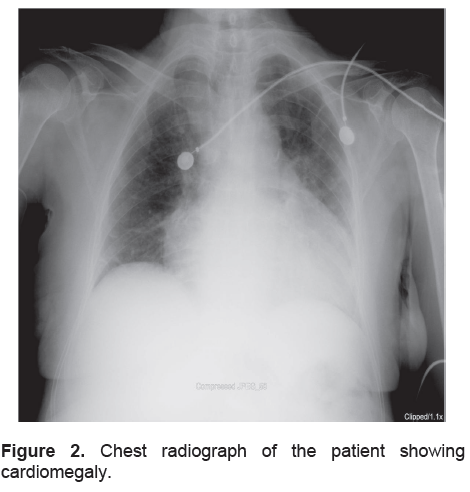

Table 1 lists the relevant laboratory results. Thyroid function testing subsequently confirmed severe hypothyroidism, with elevated TSH (163.10 mU/L) and barely detectable total triiodothyronine (T3) (<0.006 nmol/L) and total thyroxine (T4) (<12.87 nmol/L) levels. Serum electrolytes revealed a low normal serum sodium level (137mmol/L). She had leukopenia with no apparent focus of infection. She also had hypercholesterolemia (LDL-C 6.93 mmol/L) and elevated total creatinine kinase (CK-total 727 U/L). An EMG-NCV revealed focal median neuropathy at the level of both wrists compatible with carpal tunnel syndrome. Plain film of the abdomen showed ileus with fecal retention. Chest X-ray revealed cardiomegaly with no evidence of pulmonary congestion (Figure 2). Electrocardiogram on admission showed sinus arrhythmia with a heart rate of 86 beats/min and diffuse flattened T waves in all leads.

Click here to download Figure 2

Figure 2. Chest radiograph of the patient showing cardiomegaly.